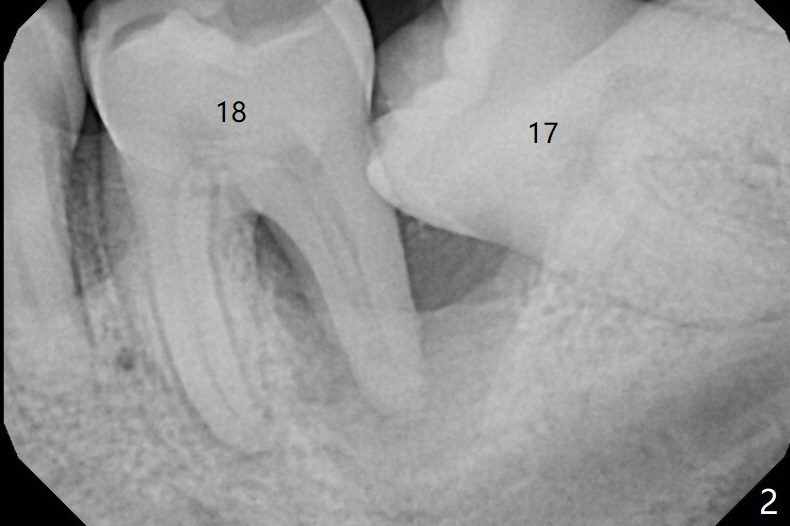

A 43-year-old man requests #17 extraction (Fig.1,2); the tooth #18 has large periapical radiolucency at the distal root. After SRP and extraction, Osteogen plug is placed in #17 sockets (Fig.3 P), while Vanilla Cancellous/Cortical Mix (allograft) 18 distal (*). The wound is closed with 4-0 plain gut suture. Similar to his son, he has crowding with #10 cross bite, #11 labioversion and a possible supernumerary tooth (11'). Seven months postop, not only does the periradicular radiolucency decrease around the distal root of the tooth #18 (Fig.4 *), but also the mesial and distal sockets of the 3rd molar heal (M, D). The patient is concerned about the sensitivity of the tooth #18, which is stable with the healthy gingiva. The sensitivity disappears 1 year postop, but there is a ~ 10 mm pocket distal of #18. Endo ice test shows necrosis. Endodontic referral is recommended. If endodontic treatment is not practical, periodontal referral is next step with laser modality.